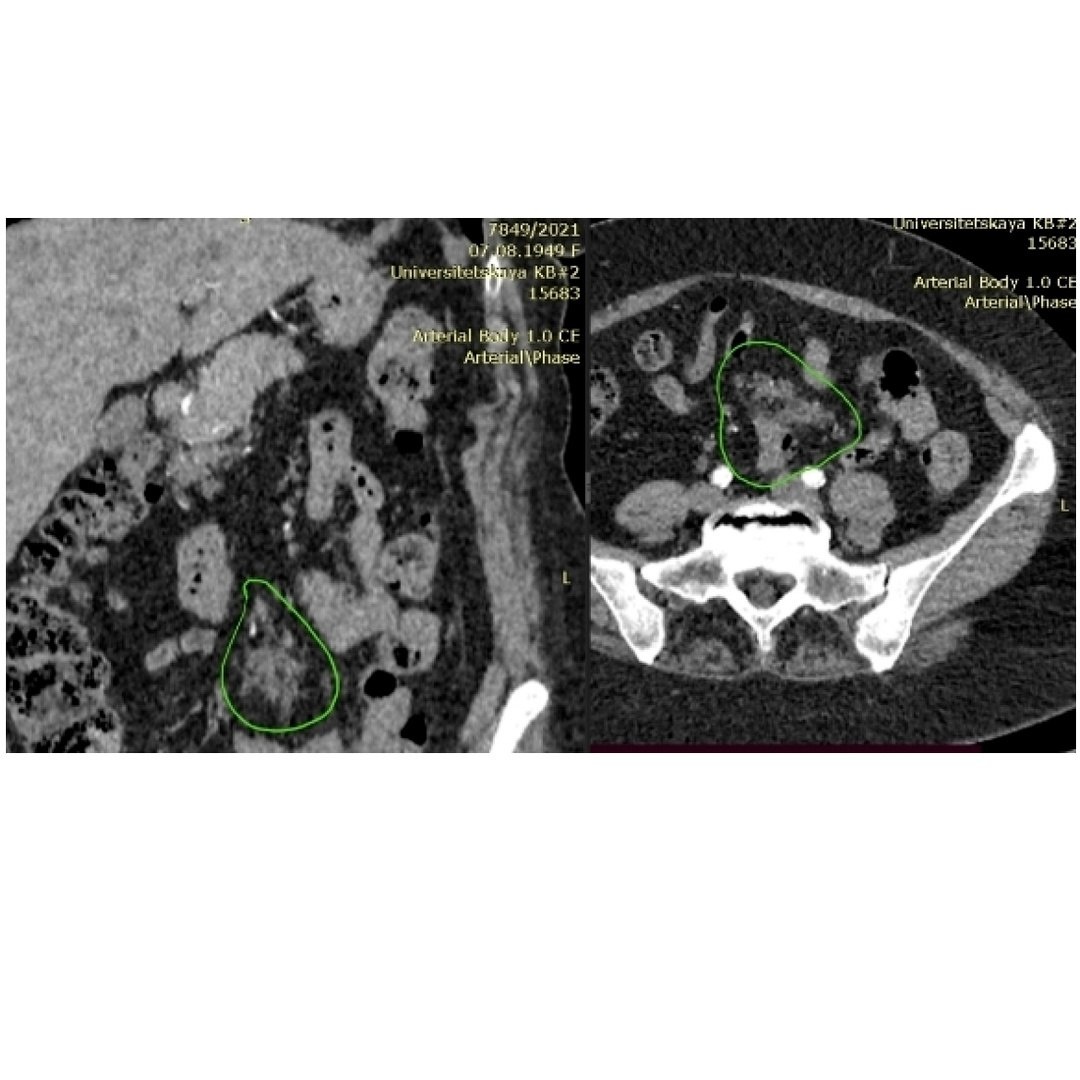

✔️в брыжейке тонкой кишки — неоднородное уплотнение мягкотканной консистенции размером 49*18*33 мм.

Лучевые диагносты расценили данное уплотнение мезентеральной клетчатки с подозрением на злокачественный рост (при учете анамнеза они не могли исключить метастатического поражения брыжейки).

На КТ подозрительные участки обведены зеленой линией.